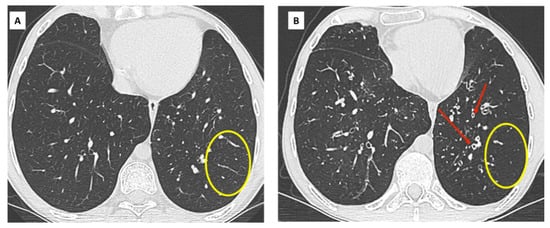

- Hota, P.; Dass, C.; Kumaran, M.; Simpson, S. High-resolution CT findings of obstructive phenotypes of chronic lung allograft dysfunction: More than just bronchiolitis oblierans syndrome. AJR Am. J. Roentgenol. 2018, 211, W13–W21. [Google Scholar] [CrossRef] [PubMed]

- Byrne, D.; Nador, R.G.; English, J.C.; Yee, J.; Levy, R.; Bergeron, C.; Swiston, J.R.; Mets, O.M.; Muller, N.L.; Bilawich, A.-M. Chronic Lung Allograft Dysfunction: Review of CT and Pathologic Findings. Radiol. Cardiothorac. Imaging 2021, 3, e200314. [Google Scholar] [CrossRef] [PubMed]

- Verleden, S.E.; de Jong, P.A.; Ruttens, D.; Vandermeulen, E.; Van Raemdonck, D.E.; Verschakelen, J.; Vanaudenaerde, B.M.; Verleden, G.M.; Vos, R. Functional and computed tomographic evolution and survival of restrictive allograft syndrome after lung transplantation. J. Heart Lung Transplant. 2014, 33, 270–277. [Google Scholar] [CrossRef] [PubMed]